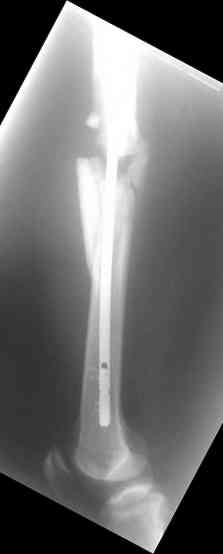

молодй человек 26лет получил С3-перелом правого бедра и легкую черепно мозговую травму (сотрясение головного мозга). Через неделю (противошоковые мереприятия и скелетное вытяжение выполнялось в ЦРБ)оперирован: БИОС бедра стержнем СнМ, Польша. Выписан со швами на амбулаторное лечение по месту жительства в г. Ижевск.Через 1месяц главным врачом больницы, со слов пациента, предложен реостеосинтез пластиной "соберем кость".

Надеюсь сейчас показать перелом, а потом синтез.

Про "кролика", конечно, не очень хорошо с точки зрения деонтологии. Но коллега, Вы думаете кто-нибудь из заядлых Nailer- ов оценит положительно этот остеосинтез? Возможно, на то были объективные причины: отсутствие штифтов большего диаметра..., штифтов, позволяющих блокировать более толстыми винтами..? А уж Plater-ы, конечено засмеют.

У данного пациента есть все основания ожидать несращения. Менять штифт (безусловно тонкий и недостаточно стабильный для этого перелома) на пластину не лучший вариант, особенно, если предполагается открытая операция. Или главный врач в Ижевске имеет ввиду длинную мостовидную пластину LCP по технике MIPO? Тогда шансов на сращение будет больше, чем сейчас, но с нагрузкой придется очень и очень подождать.

Не вижу больших оснований для пессимизма, тут все шансы на сращение есть - сделано закрыто, винтики в гвозде есть. С нагрузкой на ногу торопиться не надо только.

По моему мнению не стоит торопиться с реостеосинтезом. Через 6-8 месяцев будет видно консолидацию.

Через 3-4 месяца рекомендую начинать приступать на ногу с нагрузкой 50-80%.